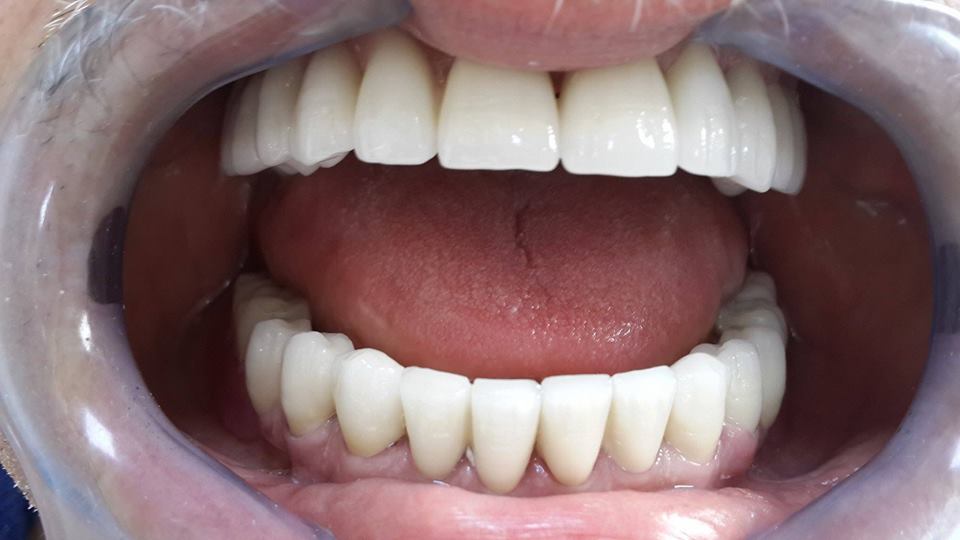

An example of complete rehabilitation of the oral cavity. Treatment included the removal of the old prosthesis, treatment of paradontitis, removal of a large cyst, implantation, clasp prosthesis.